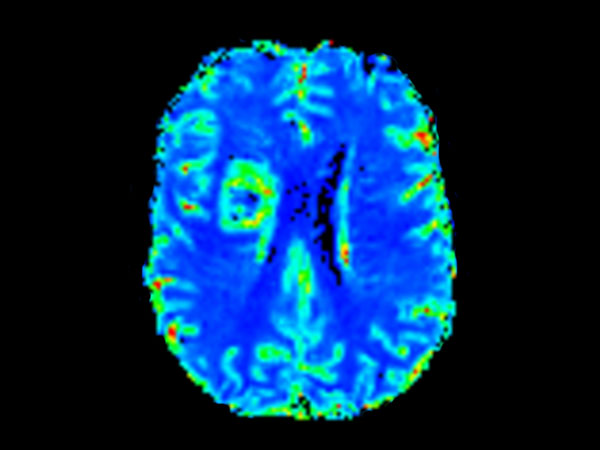

Brain with glioblastoma, incl. 3D APT

Patient with a revasculerized area with small bleedings. Diagnosed as malignant glioblastoom.

Axial T2* Perfusion (Index)